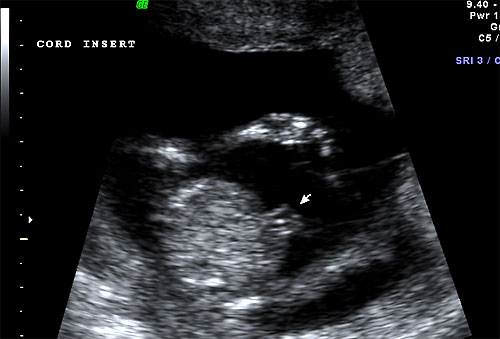

Normal 16 week fetal cord insertion site |